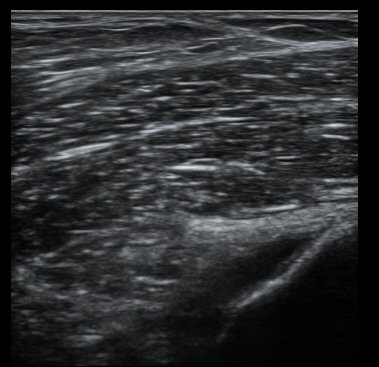

´ëÅð°ñ ¿ÜÃø°ú ¾ÕÂÊ Á¾´Ü¸é°Ë»ç¿¡¼­ ¾à°£ÀÇ ¼ö¾×Àú·ù°¡ °üÂûµÊ(±×¸² 1, 2).

¹«¸­ ³»ÃøºÎÀδë Á¾´Ü¸é°Ë»ç¿¡¼­ ³»ÃøºÎÀδë Ç¥Ãþ±ÙÀ§ºÎ Àú¿¡ÄÚ ºÎÁ¾ ¹× ½ÉÃþ±ÙÀ§ºÎ ºÎºÐÆÄ¿­ÀÌ

°üÂûµÊ(±×¸² 3, 4).